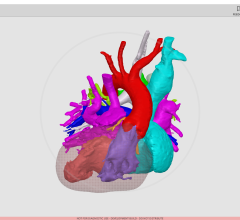

One of the new features in nordicICE v2.3 is the BOLD and DTI Wizard - dedicated to simplifying and optimizing the workflow associated with analyzing and combining Diffusion Tensor Imaging and BOLD fMRI data. This wizard provides an intuitive and easy-to-use step-by-step interface that guides the user through the process of loading, analyzing and visualizing multimodality imaging data. The new integrated Multi-Planar Reconstruction and 3D visualization interface offers unique tools for combining functional activation maps and white matter fiber tracts on a structural image volume. The resulting datasets (both fiber structures and activation maps) can be readily exported to various neuronavigation and treatment planning systems.